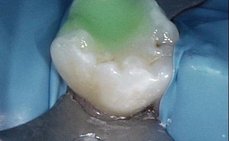

Kaz na dočasné stoličce

Kaz destruující dočasnou stoličku a dáseň vrůstající do defektu